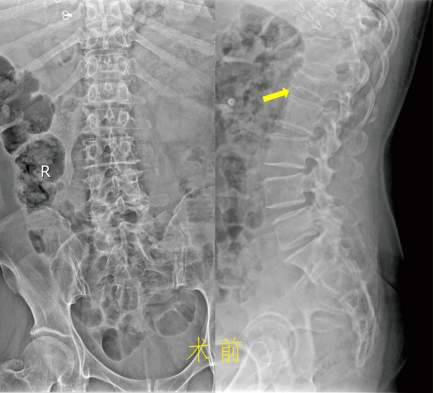

家住九江市经开区的患者王阿姨在家中做事时不慎摔倒,臀部着地,顿时感觉腰背疼痛,腰椎活动受限,并且伴随局部肿胀。随后紧急被救护车送至我院就诊,我院急诊科根据患者腰椎CT检查结果诊断为“腰椎压缩性骨折”,随即收治进我院骨科。 患者入科后,市一医院骨科主任胡斌带领骨科团队进行术前综合评估后,为患者及家属详细讲解病情及手术治疗方式。我院骨科团队为减轻患者治疗痛苦,尽早结束卧床状态,帮助患者尽快恢复正常生活,选择了手术创伤小、恢复快的“经皮植钉骨折复位内固定术”。 在骨科、手术室和麻醉科的充分准备后,在市一医院杨敏捷医师的指导下,整个手术非常顺利。术后第二天复查X线片见压缩性骨折的椎体完全恢复到了接近原来的高度,术后第五天患者就可以配戴胸腰支具下地行走了!